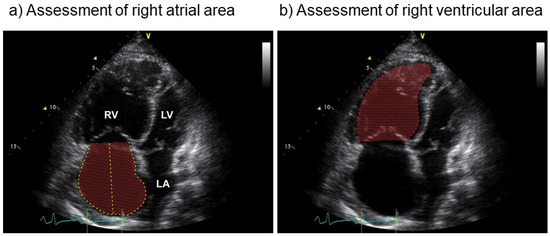

- Grünig, E.; Henn, P.; D’Andrea, A.; Claussen, M.; Ehlken, N.; Maier, F.; Naeije, R.; Nagel, C.; Prange, F.; Weidenhammer, J.; et al. Reference values for and determinants of right atrial area in healthy adults by 2-dimensional echocardiography. Circ. Cardiovasc. Imaging 2013, 6, 117–124. [Google Scholar] [CrossRef]

- Grünig, E.; Biskupek, J.; D’Andrea, A.; Ehlken, N.; Egenlauf, B.; Weidenhammer, J.; Marra, A.M.; Cittadini, A.; Fischer, C.; Bossone, E. Reference ranges for and determinants of right ventricular area in healthy adults by two-dimensional echocardiography. Respiration 2015, 89, 284–293. [Google Scholar] [CrossRef]